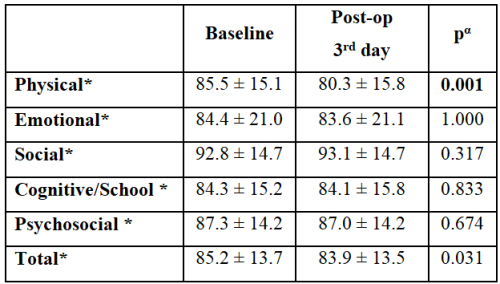

Metin Savun, Fatih Yanaral, Ufuk Çağlar, et al.

Urinary system stone disease; is a common health problem

prevalence ranging from 1-20%. The prevalence of urolithiasis

is increasing and children are more likely to experience

recurrence [,]. Although endourological treatments are

becoming widespread with the miniaturization of endoscopic

instruments, extracorporeal shock wave lithotripsy (SWL) is

widely used in the treatment of pediatric urinary stone disease.

SWL is a noninvasive, effective and reliable method []. It is

easier for children to reduce shock wave transmission due to

the smaller body volume, shorter ureter length and high ureter

compliance facilitating spontaneous disposal of stone fragments

[]. According to the European Urology Association; SWL is the

first-choice method in children with renal and ureteral stones up

to 20 millimeters [].

In pediatric patients with urinary stone disease, the stonefree

rate of SWL has been reported as 67-93% in the short term

and 57-92% in long-term follow-up studies []. However, the

complication rates of SWL are very low []. Pediatric SWL

is a painful procedure. It is often performed under sedation or

general anesthesia to reduce pain and ensure patient immobility.

Both the SWL procedure itself and the anesthesia administered

may affect the quality of life (QoL) of the child. Although there

are many studies on the efficacy and safety of pediatric SWL, to

the best of our knowledge, no published studies have explored

the association between SWL and QoL in pediatric patients.

Assessing QoL in children is critical, as it impacts their

physical, emotional, and social development, as well as family

dynamics. In this study, we aimed to determine the relationship

between pediatric SWL and patients" QoL using a validated QoL

scale.